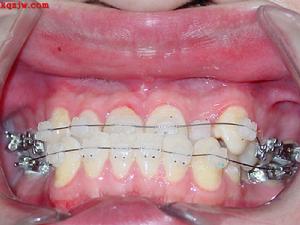

③恆牙期反合

各種非骨性前牙反合在恆牙期均能矯治,矯治方法包括掩飾性矯治和正畸-正頜聯合治療。對於骨性反合患者,採用正畸正頜聯合治療方可有滿意效果。